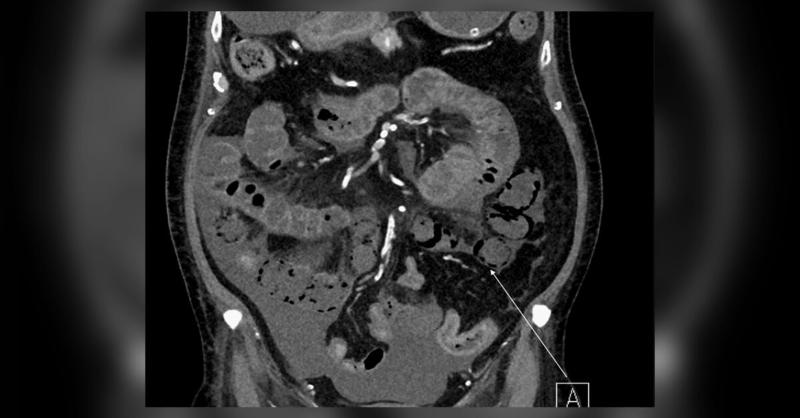

A 60-year-old man with end-stage kidney disease undergoing peritoneal dialysis, alongside uncontrolled type 2 diabetes, and hypertension, presented to the emergency department (ED) post-dialysis with loss of consciousness and breathing difficulties. Physical examination revealed a wide pulse pressure, rapid breathing, and unconsciousness. Upon admi